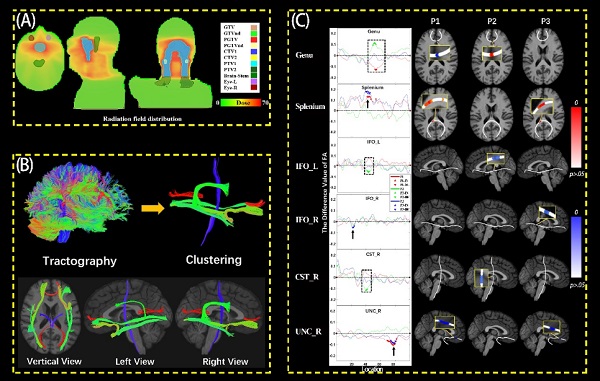

放疗是脑部肿瘤治疗的重要手段,在放疗规划中需重点考虑放疗效果与脑功能保护两个关键因素。为了达到最优的放疗质量,中科院合肥肿瘤医院从2017年起,联合放疗、影像、认知、临床专家,组成“放疗脑”联合研究团队,致力于精确放疗及迟发放射性脑损伤风险的早期评估和干预研究。项目启动以来,联合团队以鼻咽癌患者为主要研究对象,在放疗规划时,对关键脑神经核团-海马,进行充分保护,并在放疗前、放疗中及放疗后分别采集患者的MRI神经影像学数据和神经认知数据,实时跟踪放疗效果,评估放疗质量,以期建立迟发放射性脑损伤风险的早期预测模型,为最大化患者的治疗质量提供技术手段。2021年,在部分前期数据的基础上,团队采用基于纤维束的分析方法,探索了鼻咽癌患者大脑主要神经纤维束的放疗敏感性,为将来个性化放疗奠定了基础。

放疗期间白质纤维束微观形态学变化